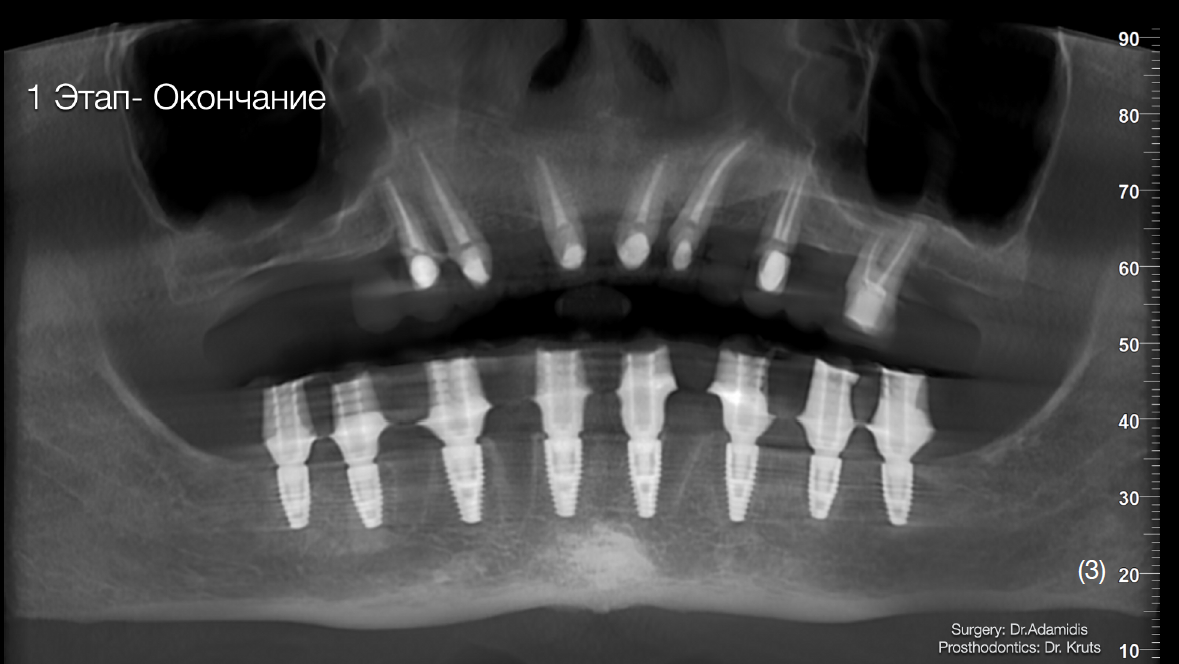

Етап 1. Робота з нижньою щелепою:

Екстракція наявних зубів та одномоментне встановлення 8 імплантатів Straumann BLT з використанням навігаційного хірургічного шаблону. В це ж відвідування було зафіксовано тимчасову конструкцію з рівня імплантатів, без використання мультиюніт-абатментів. Станом на цей момент для тимчасової реабілітації верхньої щелепи вже було виготовлено та зафіксовано провізорну конструкцію з опорою на зуби.

Етап 2. Робота з верхньою щелепою.

Через 3 місяці після першого етапу було проведено операцію на верхній щелепі. Було виконано відкритий синус-ліфтинг в першому квадранті та закритого в другому.

Матеріалом, що використовувався під час операції був Straumann Xenograft та аутологічна кістка, яка була забрана із ділянки зовнішньої косої лінії.

Одномоментно з кістковою аугментацією встановлено імплантати Strauman BLT діаметром 3.3mm в ділянках 12, 15, 17, 23, 25 зубів. Операційну рану було ушито, зворотньо зафіксовано тимчасову конструкцію на наявних зубах.